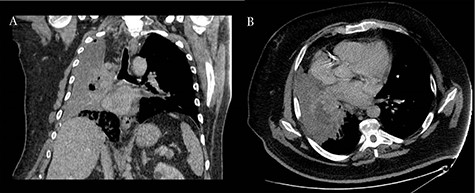

A 60-year-old smoker and obese patient (body mass index: 38.8), with a past medical history of well-controlled hypertension, hypercholesterolemia, Type 2 diabetes and mild lymphocytosis, namely, white blood cell count was 25.67 × 109/l and the lymphocyte rate was 7.60 × 109/l (diagnosed 7 years ago without any further investigation), was admitted to the local hospital complaining of significant shortness of breath and persistent continuous dry cough. Both were present at rest and exacerbated with minimal activity, resulting in decreased ability to formulate a sentence properly. A chest X-ray revealed complete consolidation of the right lung field (Fig. 1). A chest tube was inserted, draining in total 3.8 l, resulting in significant improvement of the patient’s symptoms. Pleural fluid cytology showed lymphocytic effusion with no evidence of malignancy. The chest computed tomography (CT) scan revealed consolidation of the right upper lobe with a 6-cm lesion in the hilum completely occluding the right lower lobe bronchus (Fig. 2). The right upper and middle lobe bronchi could not be reliably visualized either.

Coronal (A) and axial (B) CT scans revealing consolidation of the right upper lobe with a 6-cm lesion in hilum; the upper and middle lobe bronchus cannot be reliably visualized and complete occlusion of the right lower lobe bronchus is present.